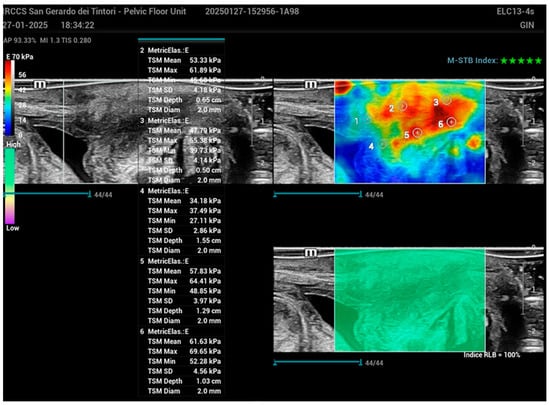

2.2. Ultrasound Examination

3.2. Comparison of BND and Young’s Modulus Among the Groups